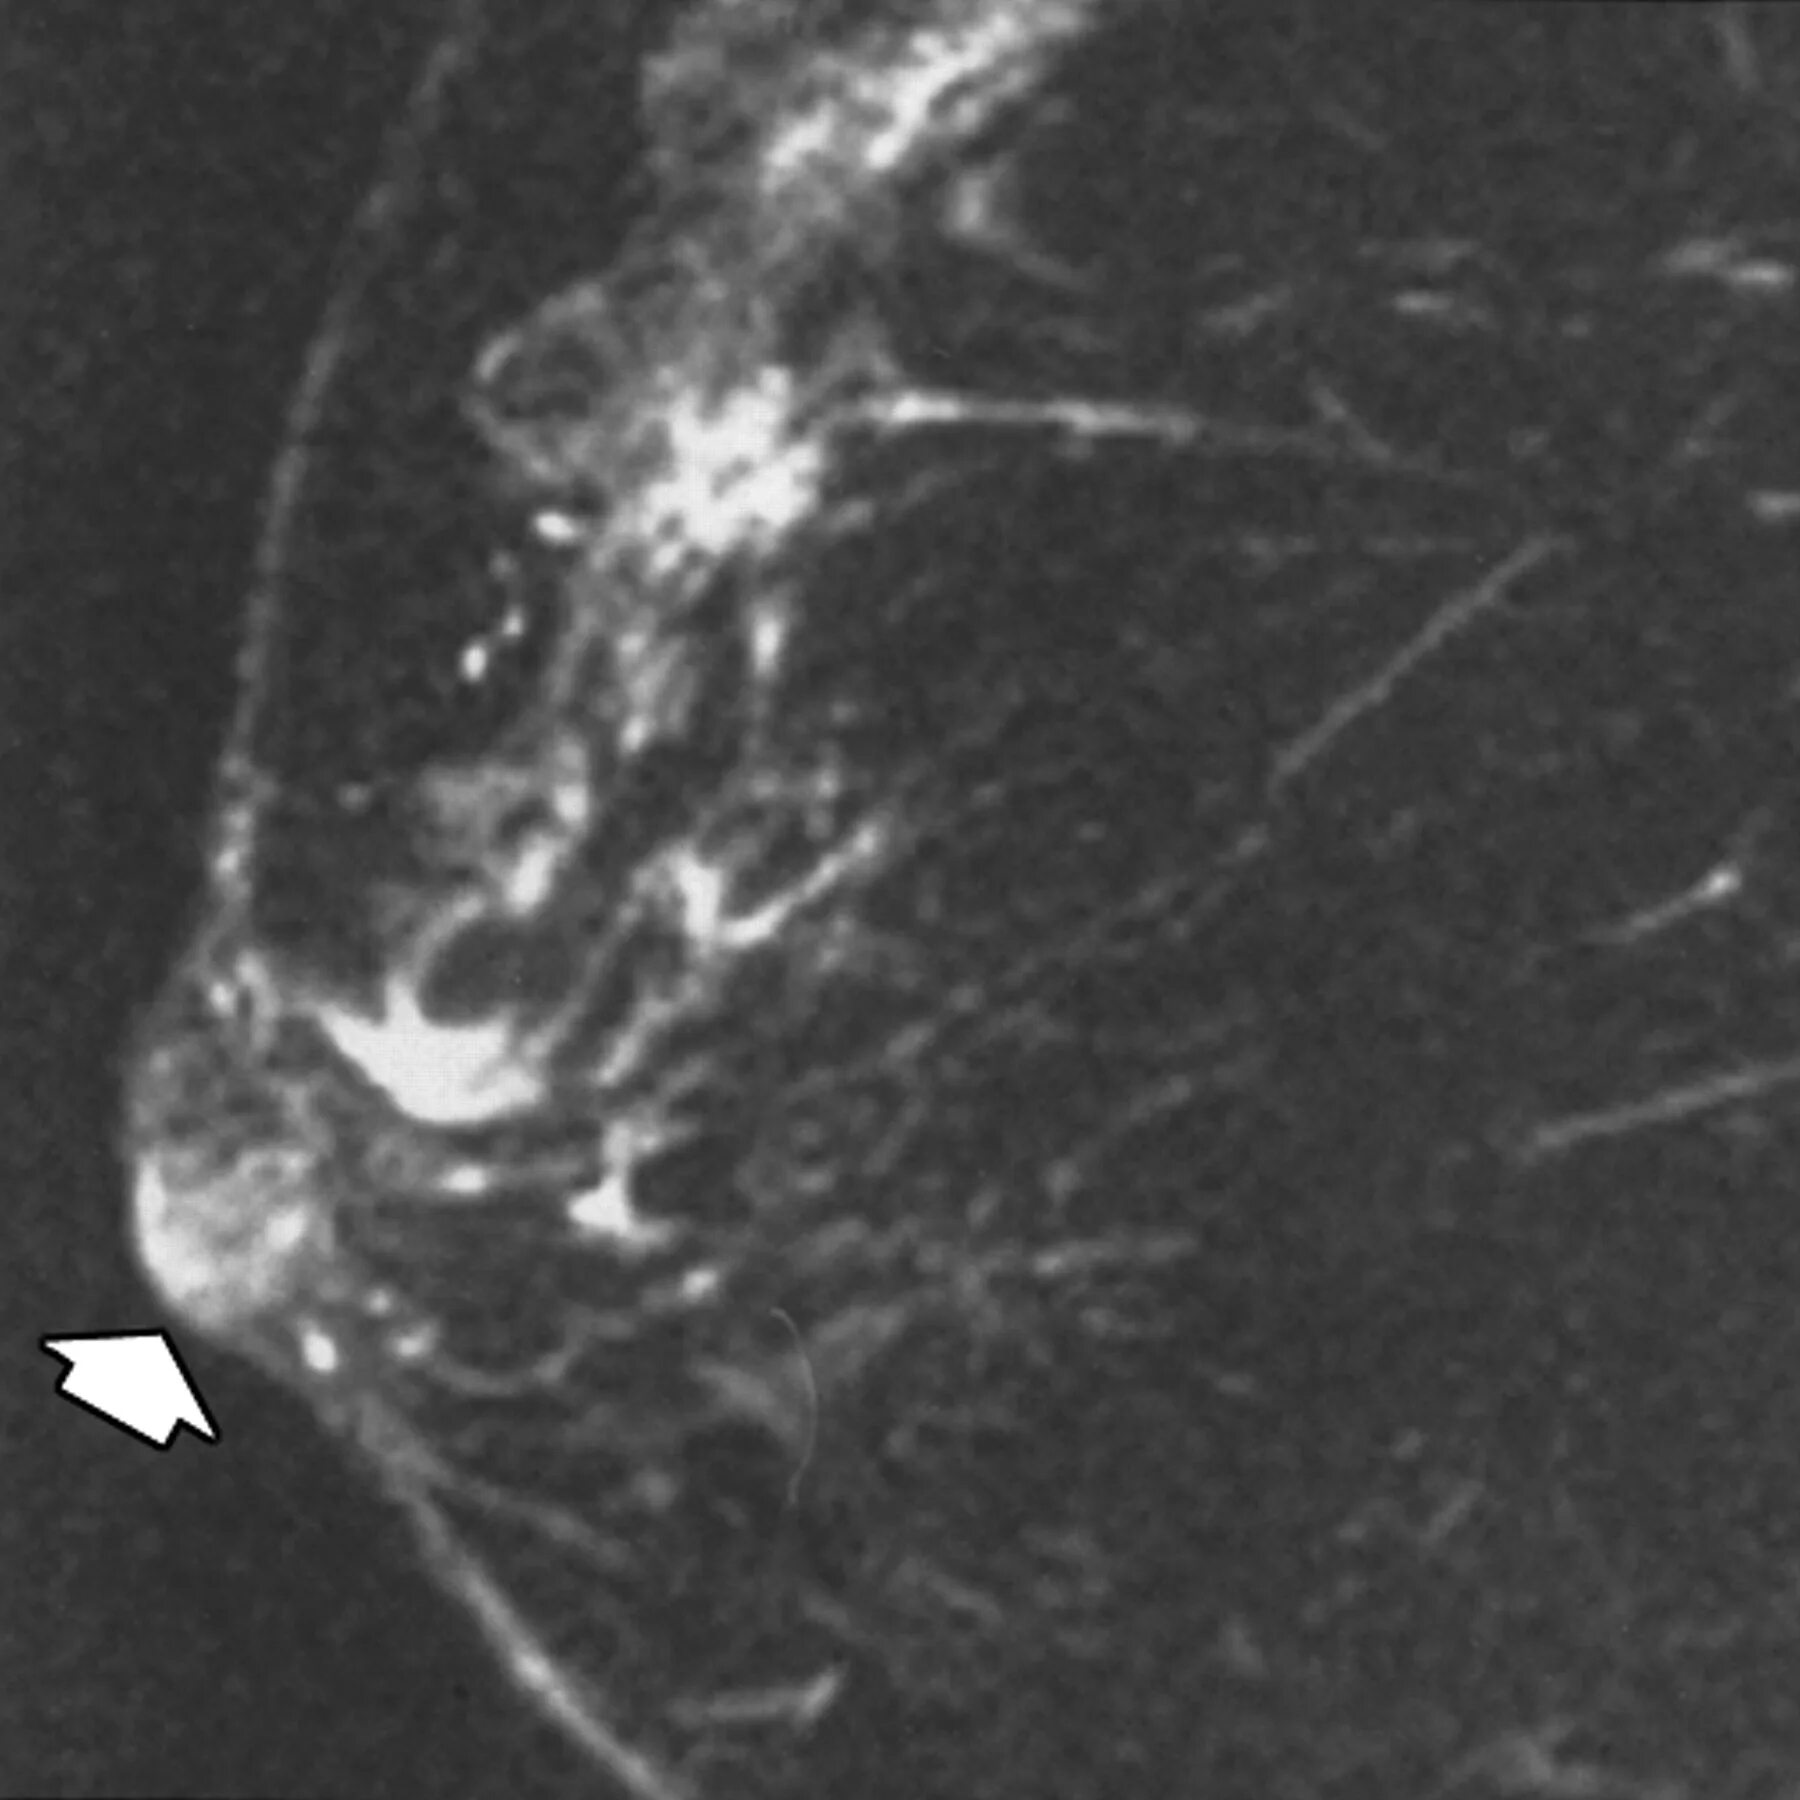

Ли аденома